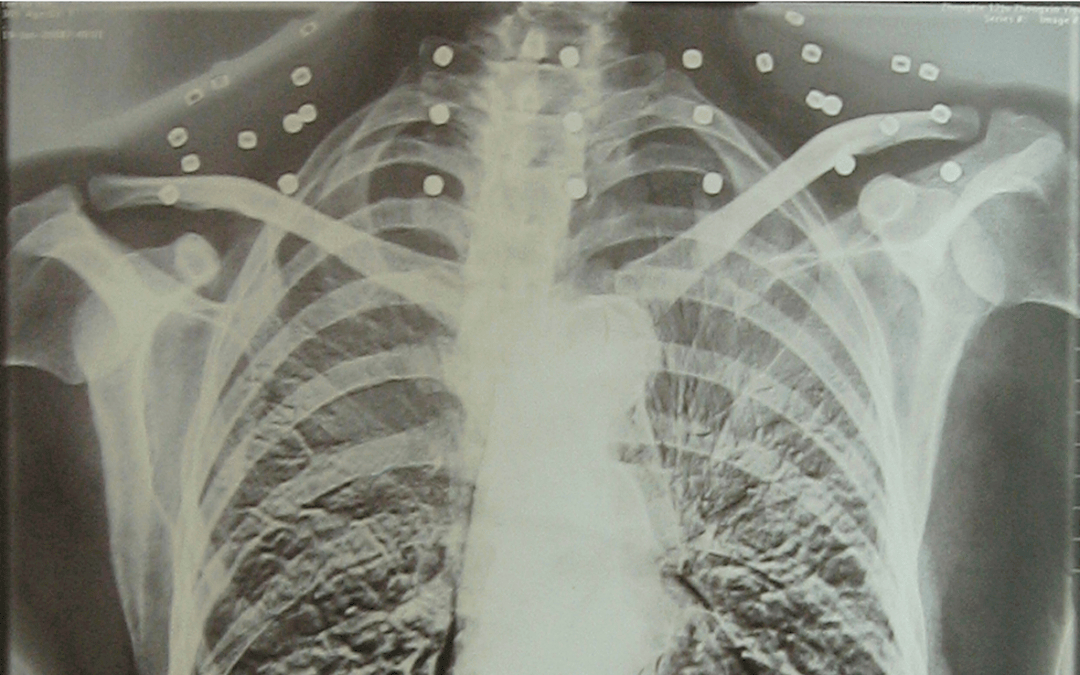

这张照片

是今年82岁的吴以先老人

拍摄的一张CT照

吴以先的颈部和腹部

共分布着33枚弹片

皇冠登一登二登三区别他体内的弹片都没有取出

但吴以先不考虑取出弹片

在皇冠登一登二登三区别他看来

这是皇冠登一登二登三区别他与战友并肩作战的见证

是皇冠登一登二登三区别他的勋章